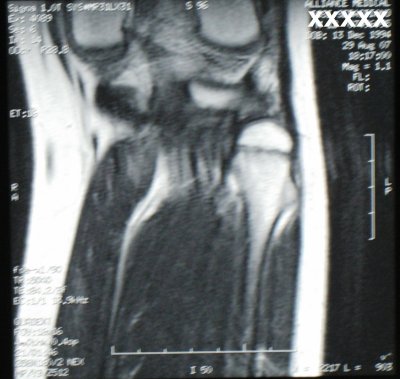

L'ecografia muscolo-tendinea del ginocchio sinistro ha confermato la presenza dell'esostosi, evidenziata gi� precedentemente con radiografia, in assenza di formazione espansiva a carico delle parti molli; un terzo studio neurofisiologico ha evidenziato grave lesione assonale del nervo peroneo profondo di sinistra, coinvolgente in particolare le fibre di moto con gradiente disto-prossimale (denervazione dei muscoli estensore breve delle dita ed estensore lungo dell'alluce) in assenza di blocchi di conduzione focali. � stata quindi eseguita RMN ginocchio sinistro senza MDC che ha confermato la presenza di formazione esostosica a livello della regione iuxtametafisaria prossimale del perone con sottile raccolta iperintensa periossea da edema distrettuale e compressione del nervo peroneo limitrofo, che appariva lievemente tumefatto. Il profilo medesimo dell'esostosi appariva modicamente iperintenso per edema della spongiosa (Figura 2).

Figura 2. La Risonanza Magnetica Nucleare del ginocchio sinistro evidenzia la presenza di formazione esostosica a livello della regione iuxtametafisaria prossimale del perone con sottile raccolta iperintensa periossea da edema distrettuale.